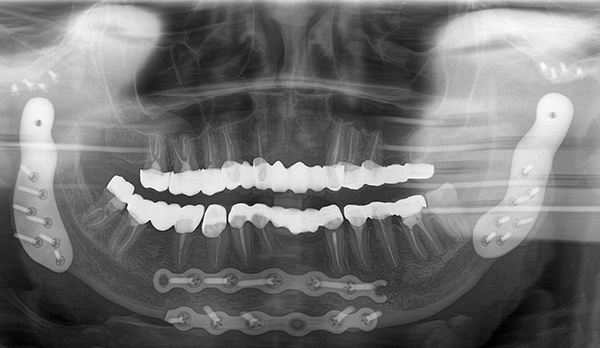

- Surgical Correction: For complex or structural joint disorders, procedures such as arthroscopy, joint reconstruction, or open joint surgery are performed with precision using advanced digital planning protocols.

- Total joint replacement: A surgical solution to restore movement and function in fused or ankylosed jaws, using custom-designed artificial joints.

Advanced diagnostic tools (3D imaging, TMJ Radiographs, digital bite analysis) to accurately identify the source of TMJ dysfunction.

- Initial Assessment & Imaging: Detailed exam and scans to evaluate jaw joints, teeth alignment, and muscle involvement.